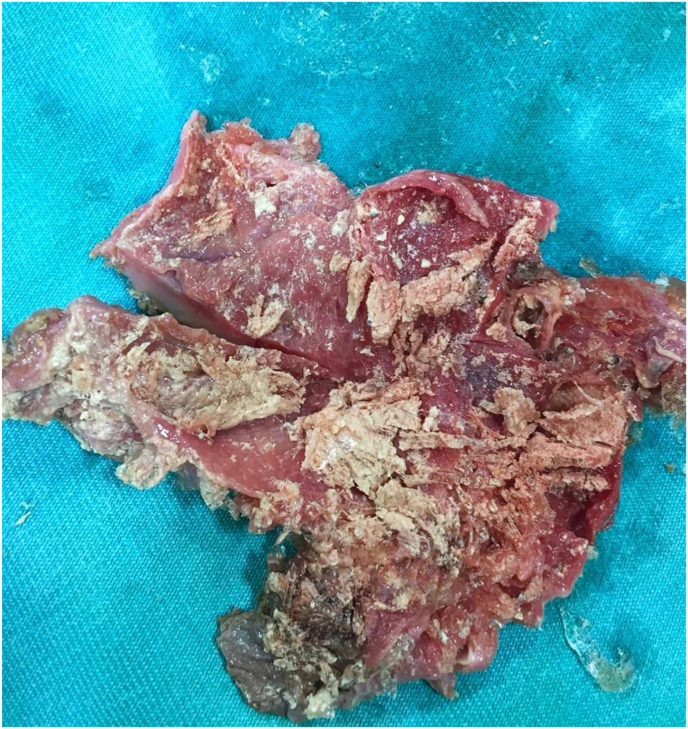

Laparoscopic surgery was performed, in which the cystic duct and artery were isolated(Fig. 1). dissection of the gallbladder revealed a ruptured hydatid cyst and the germinal layer was recognized(Fig. 2).